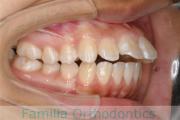

歯並びを治したいということで来院されました。下あごがやや右側に偏位して後退している、上顎前突(出っ歯)でした。上下左右から小臼歯を抜歯して、歯科矯正用アンカースクリューを併用したマルチブラケット法にて治療を行いました。約2年、24回の来院をしていただきました。

下顎の後退はいびきなどの上部気道の障害が出やすいと考えられます。